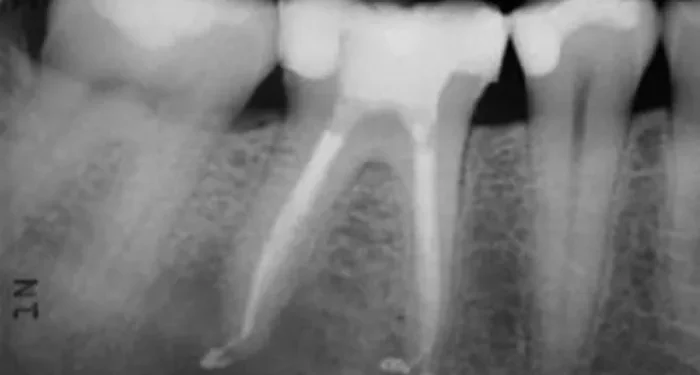

X – Rays?

X – rays are an essential tool for diagnosing root problems. They can show the dentist what’s going on inside the tooth and the surrounding bone. X – rays can reveal the presence of a deep cavity, an abscess at the root tip, a fracture in the root, or signs of bone loss due to periodontal disease. For example, if there’s an abscess at the root tip, it will show up as a dark area on the X – ray.?